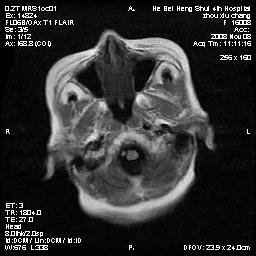

标题: MRI1883:女67岁,半年前曾患脑梗塞,治疗后好转,近3各月精 [打印本页]

女67岁,半年前曾患脑梗塞,治疗后好转,近3各月精神恍惚。

两种可能:1,转移瘤,2,脑炎,建议增强扫描

形态及整体病灶看起来首先考虑转移瘤或淋巴瘤,但奇怪的是多个病灶周围均未见显著的水肿区,这不符合这两个肿瘤的特点,结合ct表现及患者病史有个人考虑是否有皮层下动脉硬化性脑病伴多发胶质增生可能.

不像占位性病变,考虑脱髓鞘改变

皮层下动脉硬化性脑病伴脱髓鞘改变!